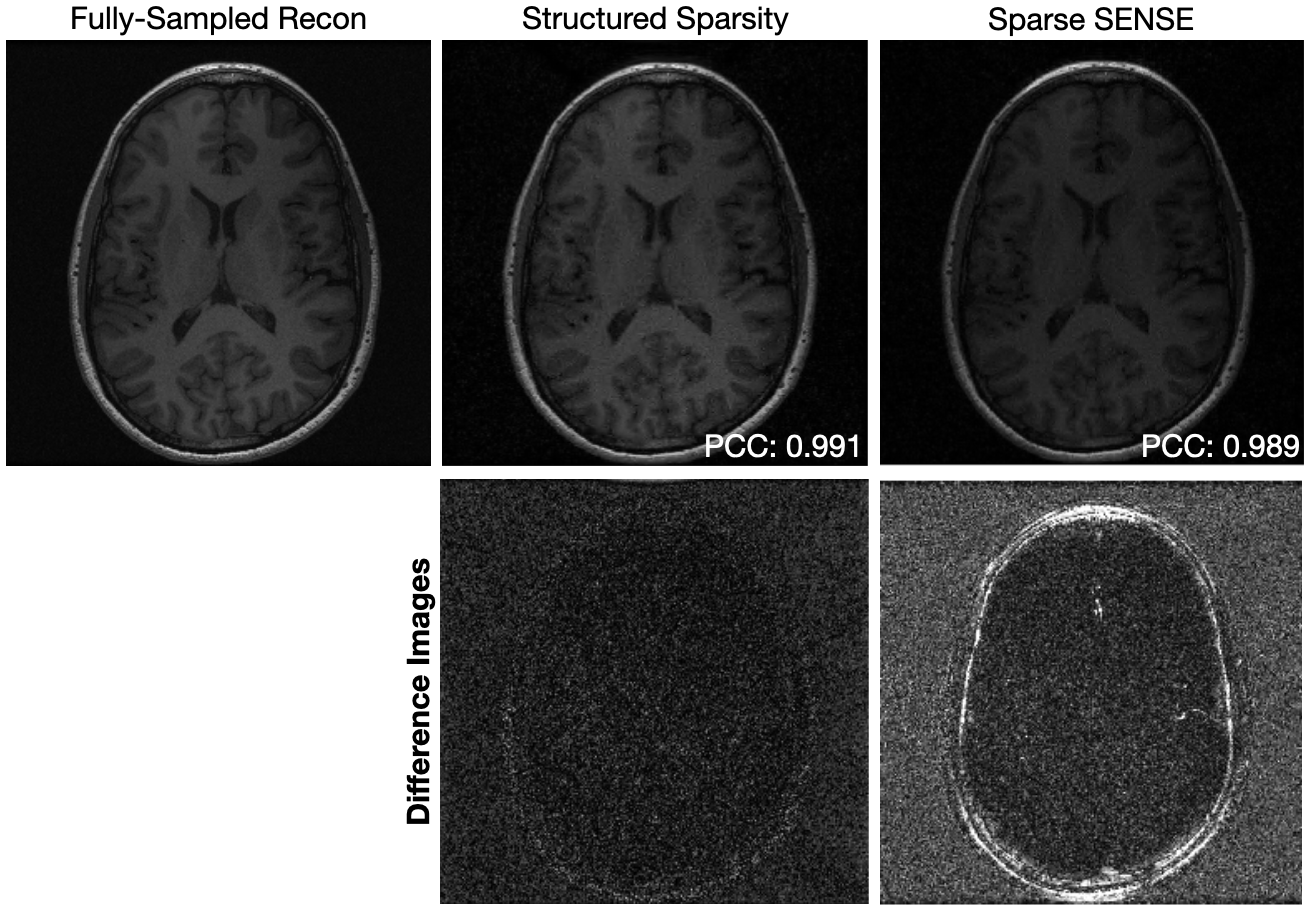

Figure 3 shows a similar comparison between the fully-sampled reconstruction, and reconstructions from 20%percent2020\%20 % of the fully-sampled data using Sparse SENSE, and parallel imaging with compressed sensing using structured sparsity for data of an axial slice of a brain collected with an 8-channel birdcage coil. As with the ankle, compressed sensing with structured sampling performs better than Sparse SENSE (PCC=0.9910.9910.9910.991 and PCC=0.9890.9890.9890.989, respectively).

Refer to caption

Figure 3: Reconstructions of an axial slice of a brain for compressed sensing with structured sparsity and Sparse SENSE. The data collected had an acceleration factor of 5555. Differences with a fully-sampled reconstruction are shown on the same intensity scale. The Pearson Correlation Coefficient (PCC) is displayed for each reconstruction. Difference images are shown on the same scale.